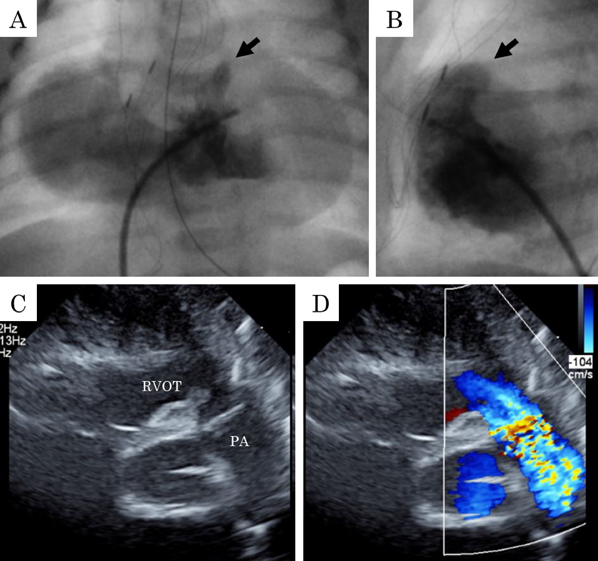

在胎35週の心室中隔欠損を伴わない肺動脈閉鎖における両側肺動脈絞扼術を用いた肺血流制御Bilateral Pulmonary Artery Banding to Regulate Excessive Pulmonary Blood Flow in Pulmonary Atresia with an Intact Ventricular Septum at 35 Weeks of Gestation